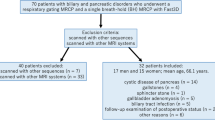

In total, 102 consecutive patients who underwent MRCP at 3.0 T, including 2D MRCP, 3D GRASE-MRCP, 3D CS-MRCP, and 3D DL-CS-MRCP, were prospectively included. Two radiologists independently analyzed the overall image quality, background suppression, artifacts, and visualization of pancreaticobiliary ducts using a five-point scale. The signal-to-noise ratio (SNR) of the common bile duct (CBD), contrast-to-noise ratio (CNR) of the CBD and liver, and contrast ratio between the periductal tissue and CBD were measured. The Friedman test was performed to compare the four protocols.